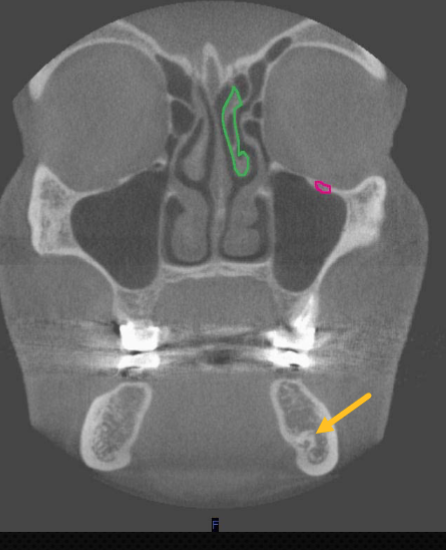

nasolacrimal duct

identify the structure

ostium (of maxillary sinus)

uncinate process

identify structure

zygomatic arch

what is indicated by the YELLOW